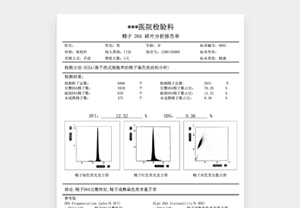

不孕不育DNA分析报告

¥60.00 -

告别千篇一律的整蛊套路,这里藏着数不清的脑洞玩法。我们精选医用级打印纸,从外观到触感都复刻真实质感,拿在手里的瞬间,逼真度直接拉满。超全素材库随心挑,覆盖多类型恶搞模板,不管是想上演 “惊喜官宣” 戏码,还是打造让人信以为真的趣味乌龙,从单人创意到多人脑洞组合,通通能满足。

关键在于无懈可击的逼真呈现。我们的打印件采用正宗医用光面纸,搭配数十款 4 周至足月的超写实设计(含双胎、三胎模板),为整蛊的可信度筑牢根基。

医用级光面工艺打印!6×8 厘米高端光面照片纸制作,还原照片级清晰画质。专为影视道具、节日恶搞、创意纪念等场景设计!